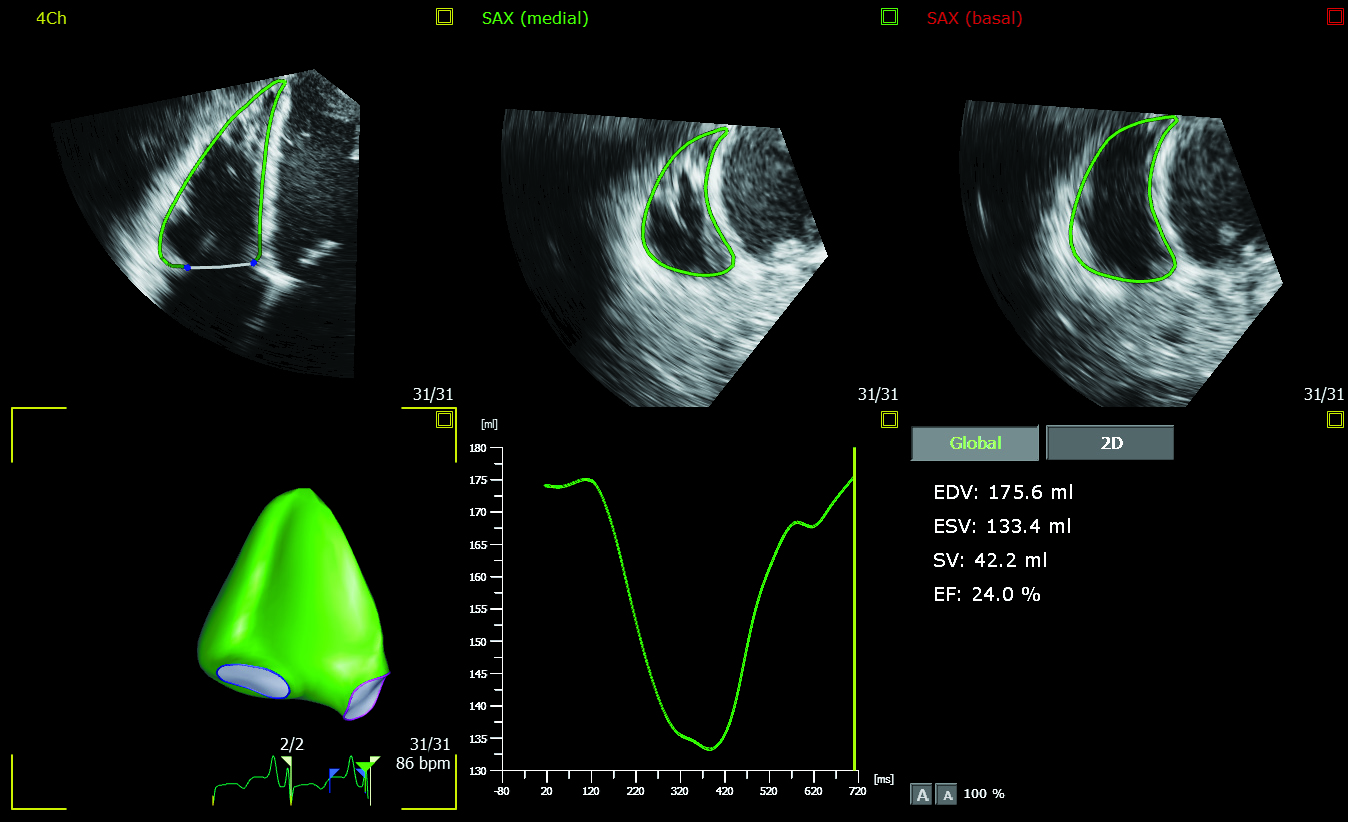

The 3D Auto RV application segments, identifies the borders of and aligns the views of the right ventricle, enabling clinicians to carry out the quantification and check the measurements in as little as 15 seconds [3]. These new applications expand on the advanced automation applications already available on the EPIQ CVx platform, including Dynamic HeartModel, which provides a clear vision of the heart’s chambers and how well they are pumping blood – specifically on the left side, where heart failure often begins. A recent study of Dynamic HeartModel published in the European Heart Journal – Cardiovascular Imaging concluded that ‘the automated algorithm can quickly measure dynamic left ventricle and left atrial volumes and accurately analyze ejection/filling parameters’ [4].